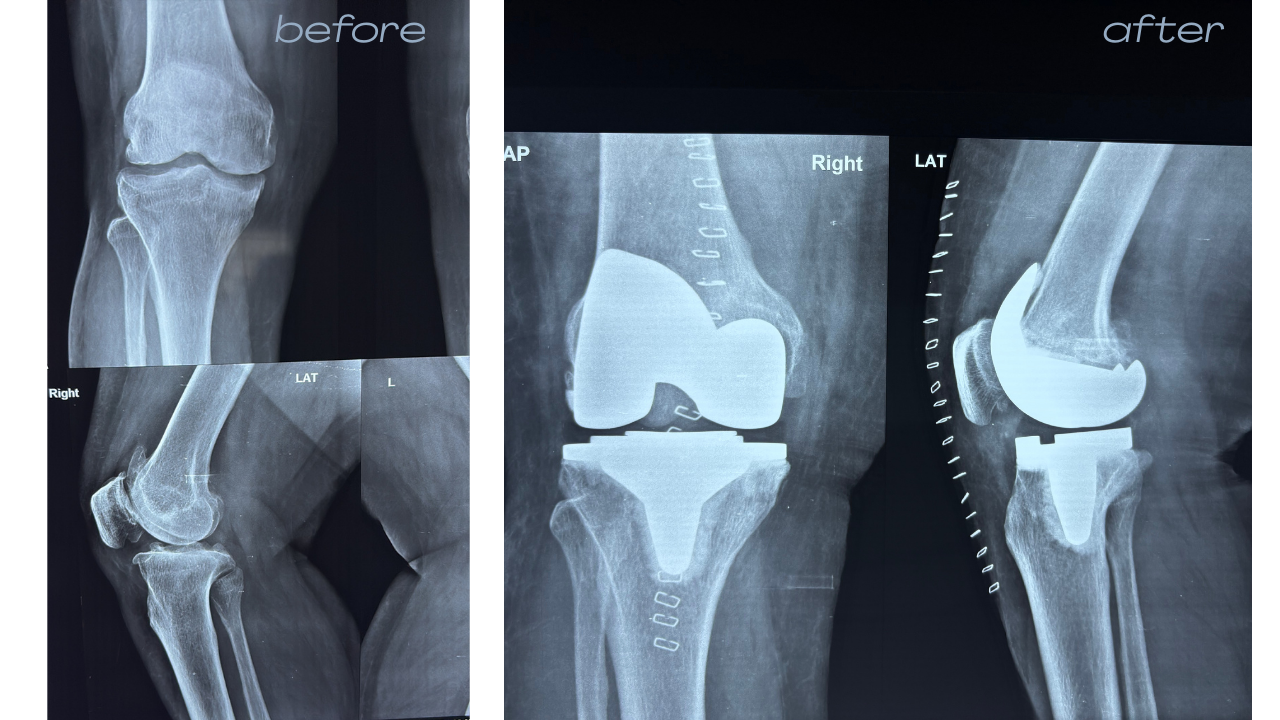

Knee & Joint Care

Comprehensive treatment for joint pain, from specialized physiotherapy to advanced Total Knee Replacement. We prioritize preserving your natural joints through medicine and rehab before recommending surgical solutions.